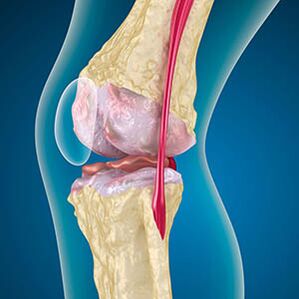

With Arthrosis, the edges of the bones, or not completely disappear.There are no receptors because the damaged tissue is not a source of pain.In the nearby structures, inflammation causes characteristic symptoms.

The body continues to restore damaged tissues, but cartilage is unevenly.As a result, there are violations that injured the other elements of the merger.The nature of osteophyte is explained by compensation for smooth joint cartilage.Another version indicates the growth of "Spurs"Due to the muscle weakening, it is associated with a joint medial or lateral constant attempt.

In the first stage of ArthosusThe accident occurs in the bone, which occurs in the bone.The growth appears in the biggest instability of the combination.Typically, patients are rarely experiencing pain or anxiety during movement.